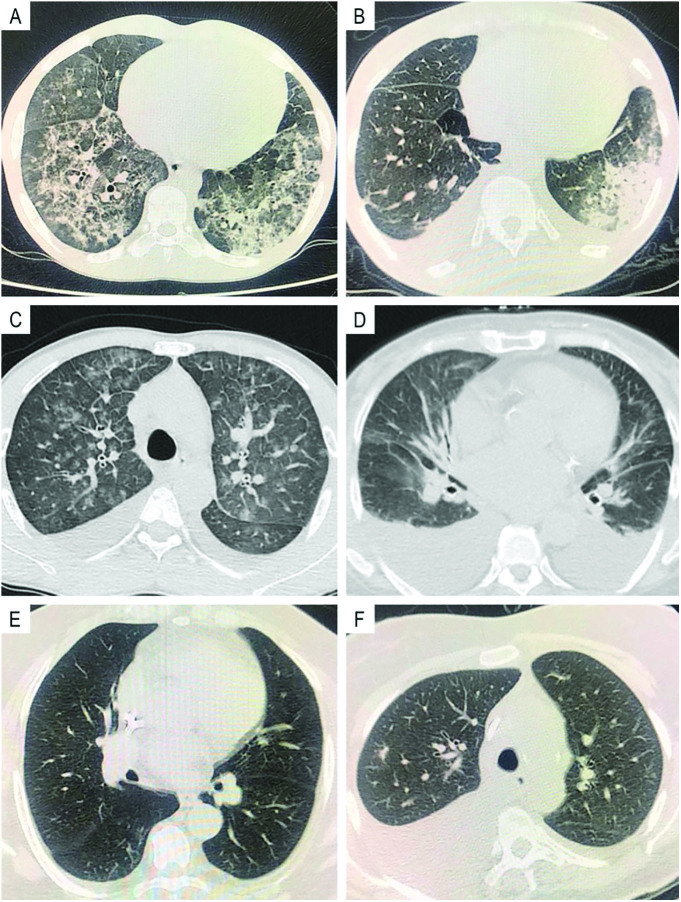

Results: We recruited 109 patients (62.3% COVID-19-positive) between March and December 2020, mean age 60 ± 12.5 years, 43% female. The most common etiology of ESKD was diabetes. Median time on dialysis was 36 months, interquartile range = 12-84. The most common pulmonary lesion on CT was ground glass opacities. Typical CT pattern was more common in COVID-19 patients (40 (61%) vs 0 (0%) in non-COVID-19 patients, p < 0.001). Sensitivity was 60.61% (40/66) and specificity was 100% (40/40). Positive predictive value and negative predictive value were 100% and 62.3%, respectively. Atypical CT pattern was more frequent in COVID-19-negative patients (9 (14%) vs 24 (56%) in COVID-19-positive, p < 0.001), while the indeterminate pattern was similar in both groups (13 (20%) vs 6 (14%), p = 0.606), and negative pattern was more common in COVID-19-negative patients (4 (6%) vs 12 (28%), p = 0.002).

Conclusions: In hospitalized ESKD patients on RRT, atypical chest CT pattern cannot adequately rule out the diagnosis of COVID-19.